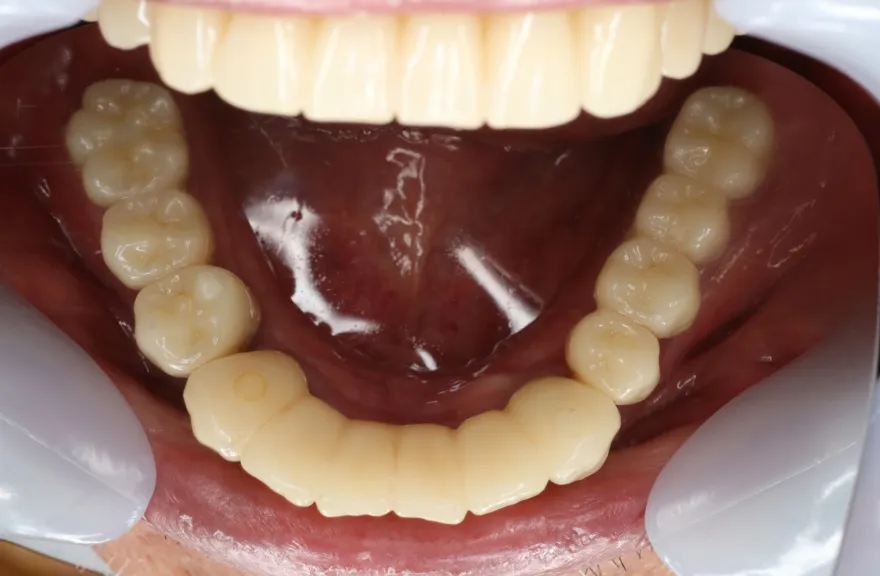

上顎は5本の歯を保険のブリッジ治療で連結してある状態でした。どの歯の状態も良くなく、今回なんとか治療を行ったとしても近いうちに再びトラブルを起こしてくることが予想されました。

下顎は9本の歯が残っており、虫歯はあるものの差し歯として使える状況でした。

しかし、患者さんとの話し合いの中で、「数年前に行った治療なのに再び全てやりかえないといけないのは単純にしんどい。もうやりかえのないようにしたい」という患者さんの強い思いが伝わってきました。

今回で完全に治療をやり切ってしまい、今後は最小限の介入で歯科と付き合えるよう、上下顎残っている歯の全ての抜歯、必要な本数のインプラント埋入、上顎は総義歯形態で対応することとしました。 - 治療のリスク

インプラント治療は決して虫歯にはなりませんしかし歯周病にはなります。

ただ、歯を失った原因を考慮する必要があります。

この方はこれまで虫歯で歯を失ってきた方でした。残っていた歯は、特に下顎の歯は歯周病に侵されることなく今に至った方です。

そういった方がインプラント周囲炎になる状況はあまり考えにくく定期的なメンテナンスのみしっかり行っておけば今後の人生においてトラブルを起こすことは心配しなくて良いかと考えます。

上顎の総義歯は時間と共にすり減り、劣化していきます。

10年ごと程度でやりかえが必要な可能性がありますが、虫歯治療のようにお口の中でドリルを使って削ったりする必要はなく、歯型をとって技工士へ製作を依頼するだけなので、治療の負担は限りなく小さいと言えるでしょう。